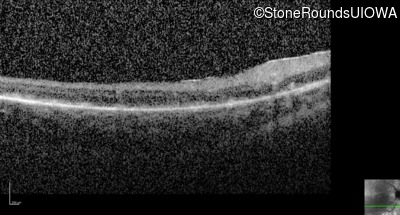

Optical Coherence Tomography - Left - 10/300 sc

Exemplar / OCT Stack

OCT Stack